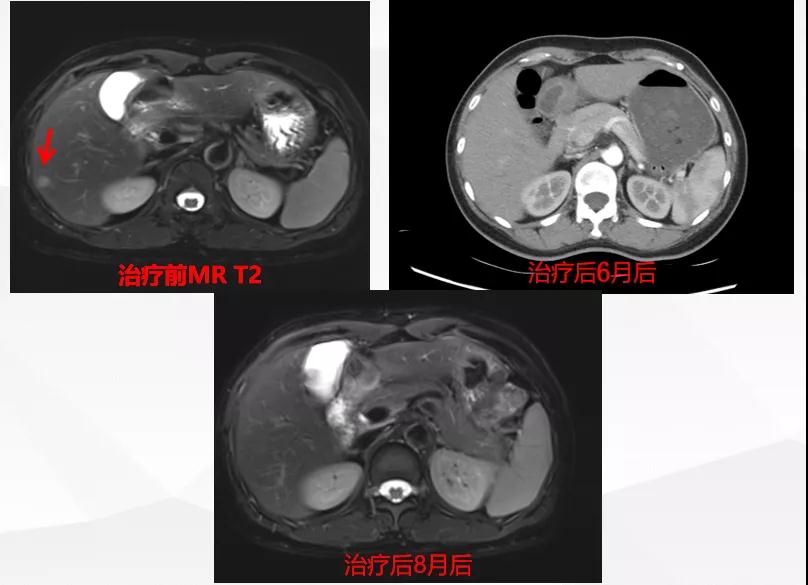

给予T-DM1治疗。治疗6个月后复查MR显示脑、肝、骨转移瘤均较前明显缩小,达到部分缓解(PR)(图2)。目前PFS已达10+个月。

患者为ⅢA期(cT3N1M0)、三阳性乳腺癌,经AC-TH新辅助治疗达到降期(ypT2N0M0)。患者内分泌+抗HER2辅助治疗结束6个月时出现转移进展(脑、肝、骨),给予THP一线治疗,因无法耐受毒副作用而改为T-DM1,治疗6个月达到肝、脑、骨转移PR,患者目前中位PFS已超过10个月,T-DM1治疗过程中仅出现轻度CIT,且可自行恢复。